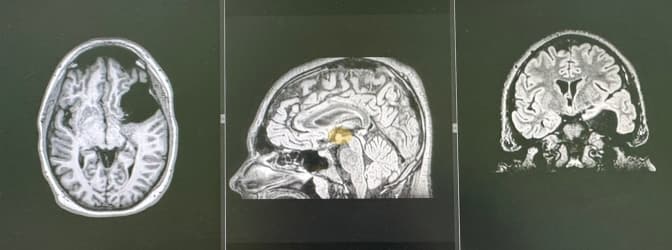

У Львові нейрохірурги провели складну операцію із видалення пухлини в мозку 53-річному Олегу, який проходив військове навчання і готувався їхати на фронт. Про це повідомили у Першому ТМО Львова.

У чоловіка за три тижні пухлина виросла до гігантських 8 сантиметрів. Водій за професією, 53-річний Олег проходив військове навчання. Час від часу він відчував, що втрачає контроль над рукою. Коли ж не зміг переключити коробку передач, звернувся до лікарні Святого Луки Першого медоб'єднання Львова.

Пухлину виявили одразу. Єдиний шлях до одужання – термінова і дуже складна операція. Дістатися до новоутвору через його розташування було непросто, але нейрохірурги завдяки сучасному мікрохірургічному обладнанню все зробили. Зараз пацієнт відновлюється після операції і налаштовується на курс лікування в онколікарні, адже пухлина виявилася злоякісною.